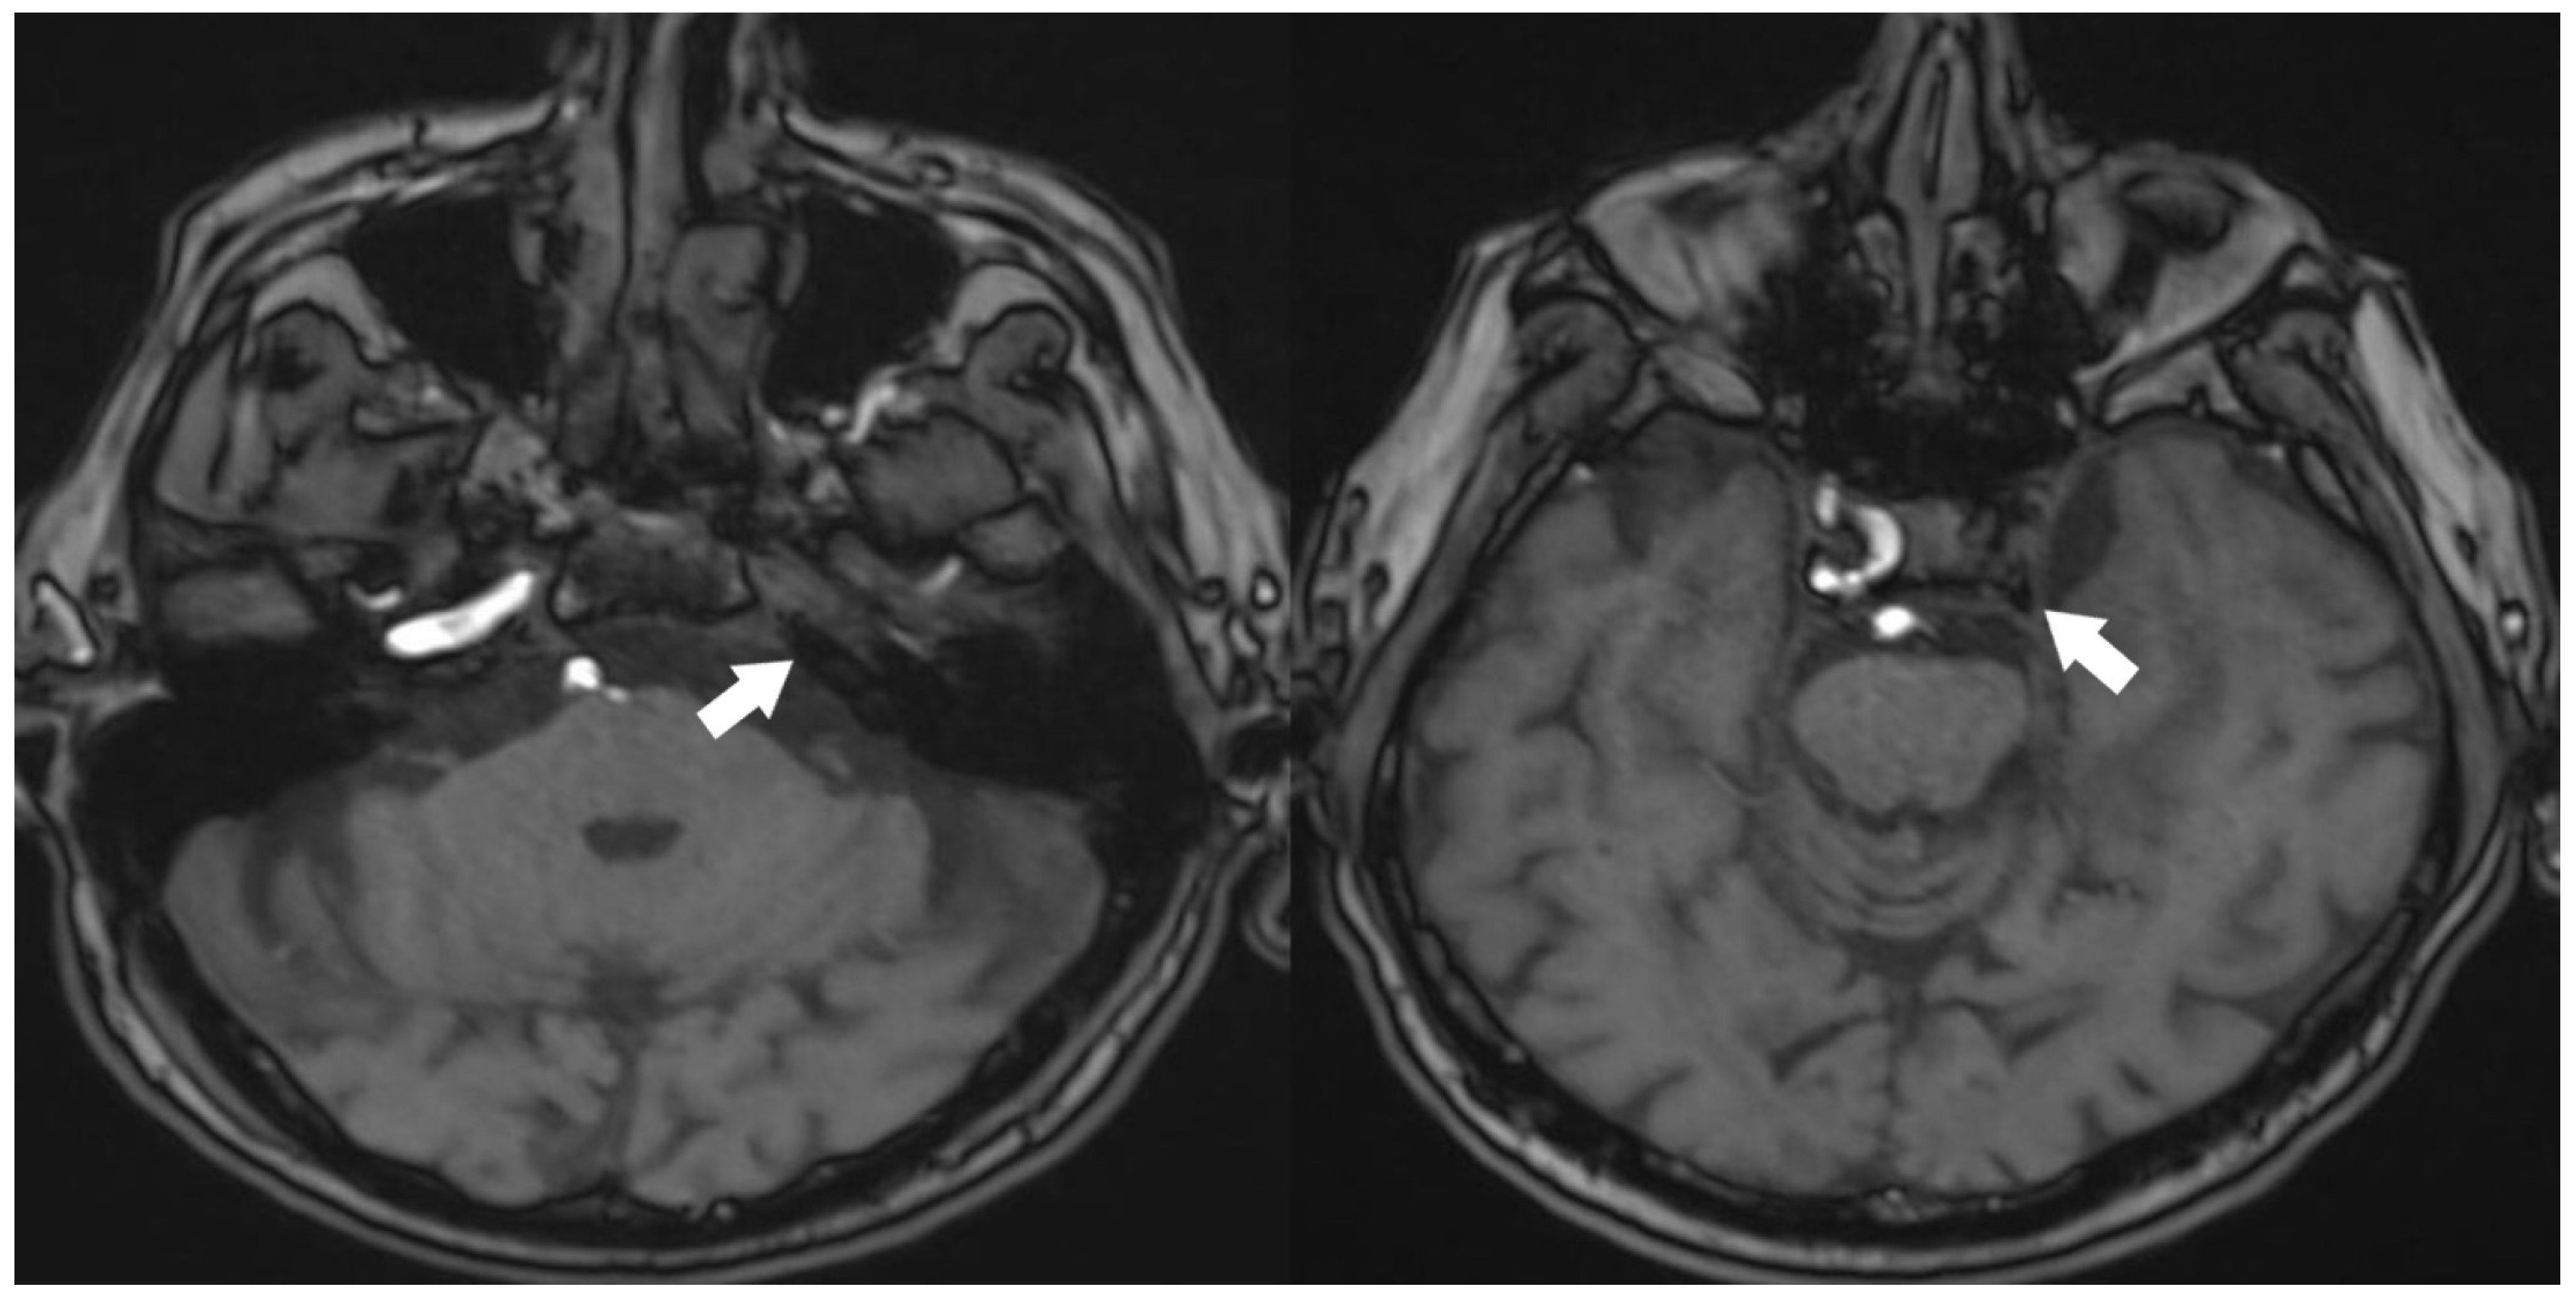

A 70-year-old male patient has presented with ongoing complaints of headache [VAS scale 6], pulsatile tinnitus [TFI level 3], and occasional dizziness. Neurological examination has revealed intact cranial nerves, bilaterally normal cerebellar function, normal deep tendon reflexes, a negative Romberg test, and preserved muscle strength. No abnormalities have been detected in other systemic examinations. Laboratory investigations showed no remarkable abnormalities. However, prior laboratory records indicated dyslipidemia for which the patient was under treatment, and he also had a known history of primary hypertension. Cranial MRI and MR angiography have demonstrated an absence of flow in the left internal carotid artery (Figure 1 and Figure 2).

Figure 1.

Absence of the left internal carotid artery on cranial MRI angiography [Time of Flight images (TOF), White arrow: no contrast filling in the carotid siphon].

Figure 2.

TOF 3D imaging of cranial MRI angiography [White arrow: no contrast filling in the carotid artery].